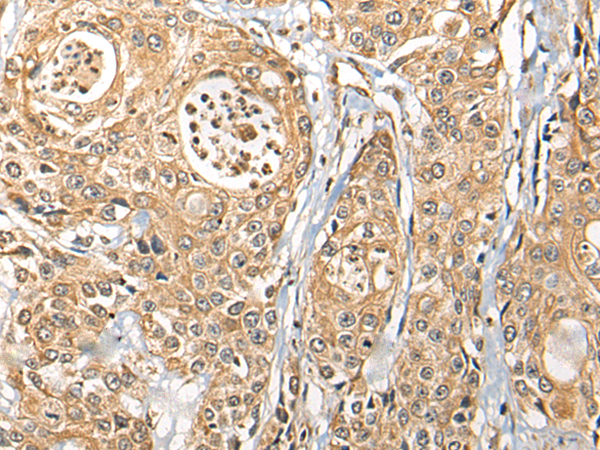

分类: 科研抗体货号: P09430别名: CAMKKA应用: WB,IHC反应种属: Human, Mouse, Rat